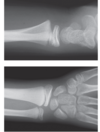

abnormalities

**1. galaezzi fracture** 2. radial fracture - transverse, displaced medially and dorsally, shortened, volar angulation 3. distal radial ulna dislocation

50

managment for galaezzi fracture

1. analgesia eg 2.5mg iv moprhine 2. reduction 2. above elbow backslab 3. elevation 4. ortho for orif